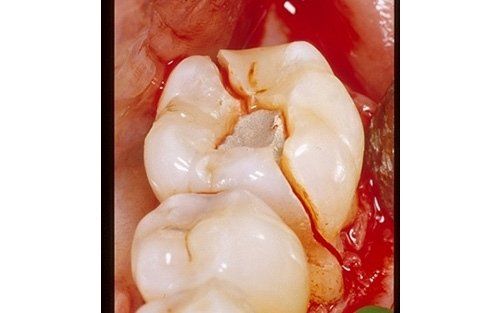

Vertical root fracture, on the other hand, is one of the few conditions that leave no doubt about treatment: once diagnosed, extraction is the only possible treatment. This type of fracture should not be confused with other types of root fractures, such as post-traumatic ones, which, on the contrary, have a high success rate. Vertical fracture, however, is a fracture line, often starting from a coronal fissure (as described above), creating a continuity solution between the intra- and extra-radicular environments, that is, communication between these two environments, creating the conditions for an infection.

The root is no longer protected, and inflammatory-infectious processes that cannot be cured set in. Patients usually do not report severe pain but discomfort they did not experience before. This condition is one of the main reasons for replacing a single tooth with a dental implant. Sometimes immediate implant placement, i.e., implants inserted simultaneously with tooth extraction, may also be possible. Consult the "Implantology" section to assess treatment options in such cases.